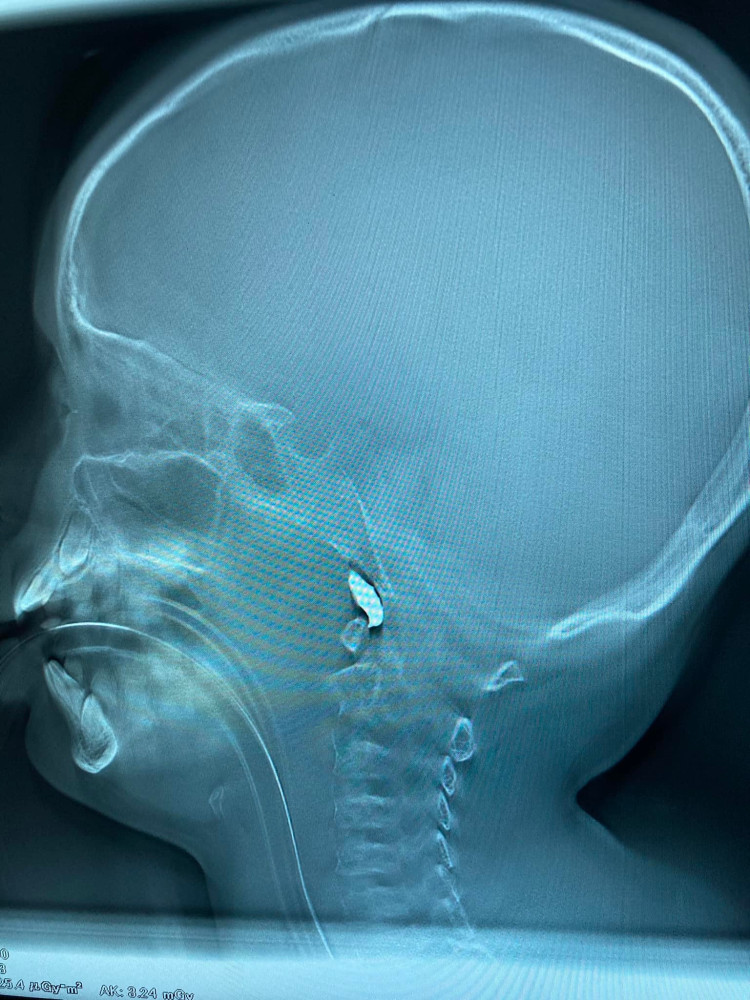

В Харькове врачи спасают десятилетнего мальчика: в его голову попал осколок снаряда

Харьковские врачи борются за жизнь десятилетнего мальчика. Во время вражеского обстрела в голову ребенка попал осколок снаряда .

«Еще один мальчик 10 лет. Минновзрывное. Снаряд влетел в помещение. Работаем», — пишет врач Александр Духовский.